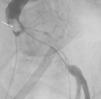

Foi orientada para angioplastia primária, não sendo passível a sua execução por via radial pela tortuosidade da artéria subclávia (Figura 1A). O acesso femoral foi dificultado pela ausência de pulso, sendo a punção guiada por contraste (Figura 1B e 1C); constatou‐se oclusão da ilíaca externa, ultrapassada utilizando uma guia hidrofílica. Observou‐se oclusão do segmento médio da coronária direita por trombo (Figura 2A), sendo realizada trombectomia (Figura 2B).

Cateterismo esquerdo: (A) cateterização por via radial impossibilitada pela tortuosidade da artéria subclávia, que impedia a progressão do fio‐guia; (B) punção da artéria femoral esquerda guiada por contraste; (C) durante a cateterização por via femoral, era aparente uma estrutura (seta) filiforme e móvel, sugestiva de trombo.